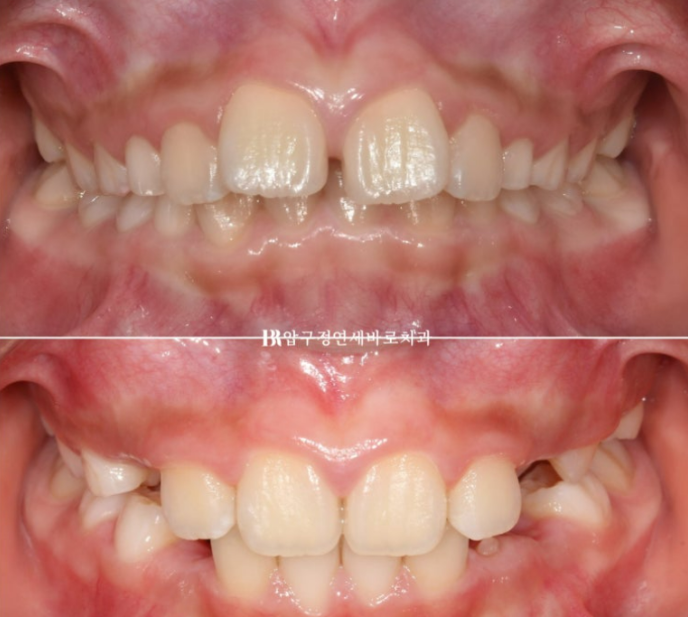

23.04

가장 먼저 보이는 것은 앞니 사이가 벌어진 것 이지만

이 벌어짐은 송곳니가 나오면서 모이기도 하기 때문에 큰 문제는 아닙니다.

그보다는 윗니가 아랫니를 많이 덮어 아랫니가 잘 보이지 않습니다.

과개교합 이라고 합니다.

윗니 아랫니 중심선이 맞지 않는 중심선 불일치도 보입니다.

옆에서 보시면 윗니 돌출이 심해보입니다.

하지만 골격 분석을 해보면 아래턱이 작아서 그렇게 보이는 것 입니다.